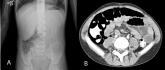

ArticleBenign Pneumatosis IntestinalisAuthor:Erich C. Maul, DOPublish date: September 14, 2009Read More